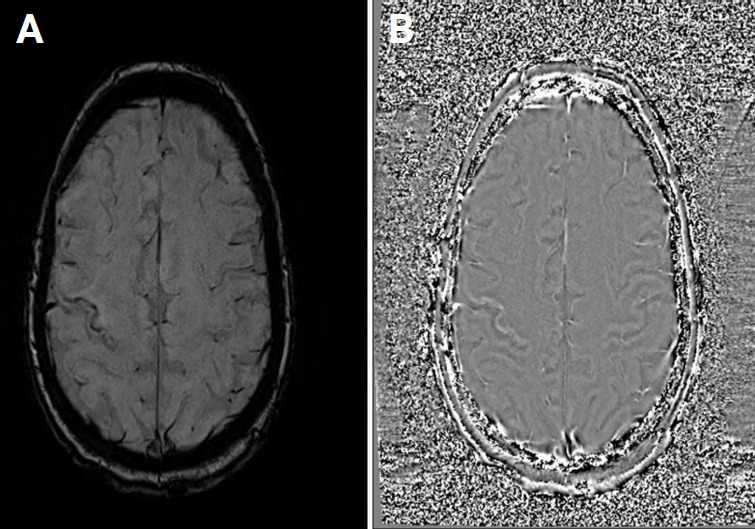

我们描述的情况下,一个47岁的妇女谁是困惑和抱怨左无力时,她提出了我们的机构。患者接受了头部计算机断层扫描,怀疑最近发生的缺血性发作(亚急性期)。患者住进神经内科,接受了磁共振成像(MRI)和造影剂治疗。临床和实验室结果以及MRI特征,特别是在敏感性加权成像(SWI)序列中出现低信号边缘,与进行性多灶性白质脑病(PML)的诊断一致。淋巴细胞减少导致免疫抑制,患者随后被诊断为先前未记载的艾滋病。我们的目的是在免疫功能低下的艾滋病患者中报道这一罕见的PML病例,描述其主要的MRI特征和SWI序列的可能作用。

We describe the case of a 47-year-old woman who was confused and complained about left-sided weakness when she presented to our institution. The patient underwent a head computed tomography that raised the suspicion of a recent-onset ischemic episode (subacute phase). The patient was admitted to the neurology department and underwent a magnetic resonance imaging (MRI) with contrast medium administration. The clinical and laboratory findings and the MRI features, particularly the presence of a hypointense rim in the susceptibility-weighted imaging (SWI) sequences, were consistent with a diagnosis of progressive multifocal leukoencephalopathy (PML). Immunosuppression was observed as a result of lymphopenia, and the patient was subsequently diagnosed with previously undocumented AIDS. Our aim is to present this rare case of PML in an immunocompromised patient with AIDS, describing the main MRI features and the possible role of SWI sequences.